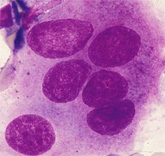

形質細胞 plasmocyte 核網と車軸状核が所見です. |